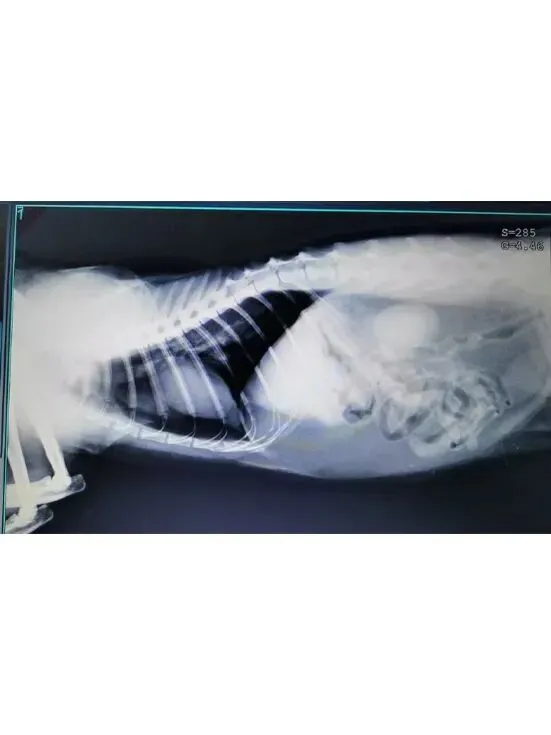

志愿者发现鸡腿蜷缩在楼梯底下不断嚎叫,且后腿无法动弹,于是当天抓捕送医。

就医检查:鸡腿后肢在医生被触摸时仍有痛觉反应,经判断大概率为盆骨骨折,且右后脚带有明显伤口,具体情况需拍摄X光片来确定。鸡腿连袋重:4.95kg。

盆骨X光片:盆骨粉碎性骨折,因十号的生化血常规和SAA指标达标,于是准备12号进行手术。